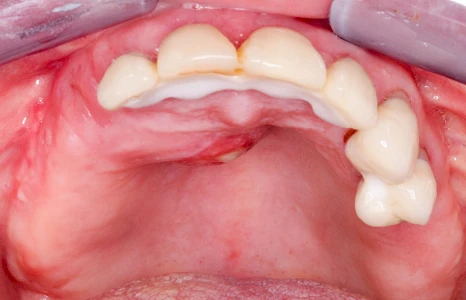

Milchiges bzw. gelbliches Sekret im Bereich der Speichelausführungsgänge entweder an den Wangeninnenseiten auf Höhe der ersten großen Backenzähne im Oberkiefer oder unter der Zunge können auf Entzündungen der großen Spreicheldrüsen hinweisen. Ebenso Schwellungen bzw. Auftreibungen, Rötungen oder spürbare Wärme einseitig unterhalb eines Ohrs und im Bereich des Kieferwinkels.

Einzündungen der kleinen Speicheldrüsen im Gaumen fallen dagegen durch kleine punktförmige Rötungen auf. Wenn ausreichende Flüssigkeitszufuhr und ggf. sanftes Massieren der Speicheldrüsen und der Ausführungsgänge (z. B. Parotitisprophylaxe) keine Verbesserung erzielen lassen oder wenn zusätzliche Symptome wie z. B. Fieber auftreten, sollte ein Arzt oder Zahnarzt hinzugezogen werden.